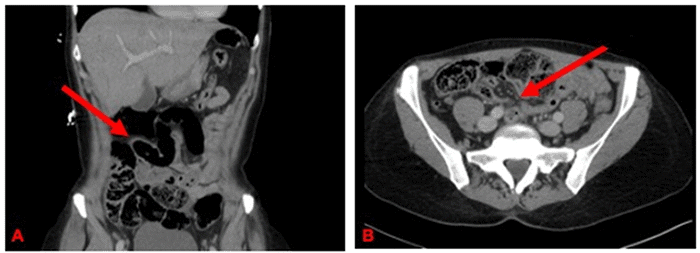

The patient was started on crystalloid fluids for hydration, and due to a childhood history of cleft palate repair, the initiation of decompression with a nasogastric (NG) tube was deferred. Based on imaging and physical examination findings, diagnostic laparoscopy was considered the appropriate initial evaluation method. During laparoscopy, multiple dilated small bowel loops were observed. Further exploration revealed a dense adhesive band extending from an antimesenteric diverticulum to a point on the small bowel mesentery, causing an internal hernia with entrapped small bowel. The hernia contents were reduced, and the band was divided using electrocautery (Figure 2). Palpation of the diverticulum and adjacent bowel did not reveal an internal mass. A stapled diverticulectomy was performed on the soft and broad base of the diverticulum. Postoperatively, the patient progressed appropriately, experienced no additional pain requiring management, and was deemed suitable for discharge the next day. Final pathology confirmed benign enteric tissue, consistent with a Meckel’s diverticulum.

Figure 2. Intraoperative Laparoscopic Images. Published with Permission

Adhesive band originating from Meckel’s diverticulum and extending to the small bowel mesentery. In the initial view (A), the band forms an internal hernia, entrapping small bowel loops. Subsequent to division (B), the hernia is resolved